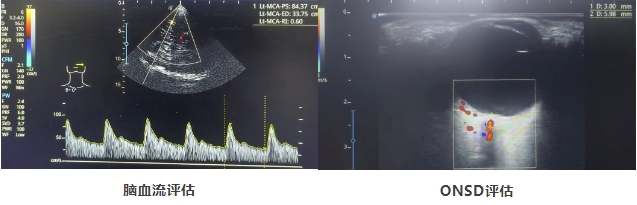

近日,江西省人民医院(南昌医学院第一附属医院)重症医学科援疆医生黄翠兰指导阿克陶县人民医院重症医学科成功开展TCCD无创脑监测技术,为多名神经重症患者实行了经颅彩色多普勒超声(TCCD)检查,为神经重症病人脑结构、脑血流及颅内压的评估提供可靠依据、更好的指导临床治疗。

神经重症患者的治疗一般围绕颅内压、脑血流监测为导向,特别是重型颅脑损伤患者更是如此。无创颅内压监测花费小、不易感染、禁忌症少,有较高的特异性,同时还可实时显示和监测脑血流,脑结构的变化,个体化决定患者最合适的治疗方案,指导治疗和协助预后判断,提高神经重症患者的抢救成功率。

TCCD技术的成功开展,解决了神经重症患者生命体征不稳定、严重骨折不便于搬动,经济条件不允许、时间紧急、凝血机制异常、多脏器功能不全等无法行有创颅内压监测的难题。该技术的开展,增加了神经重症的监测手段,提高了神经重症个体化治疗效率,也推动了阿克陶县人民医院重症医学科多模态脑监测的快速发展。